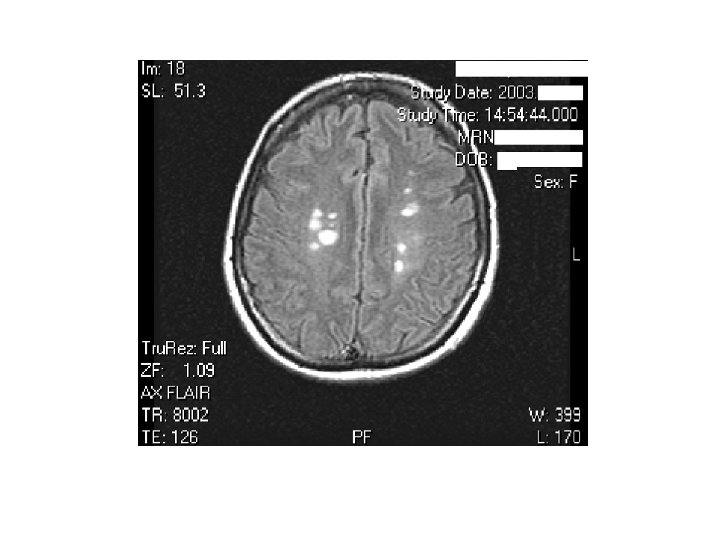

MRI BULGULARI • Periventriküler ak maddede plaklar • Serebellum / beyinsapı / servikal ve torakal spinal kord • Kontrast madde (Gadolinium) tutulumu aktif lezyon varlığını gösterir – Her zaman hastalık aktivitesinde artış ile korelasyon göstermez

MRI • MRI anormalliği: – Kesin MS’de %90 – Olası MS’de % 70

AK MADDE LEZYONLARI